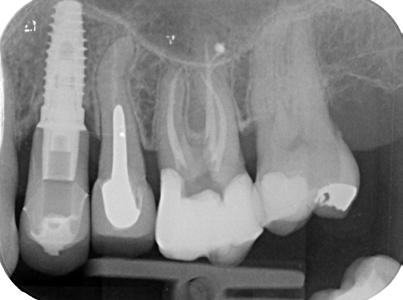

21. ábra: Kiindulási felvétel. Az elhalt felső nagyőrlőfog rágás során panaszokat okoz a páciens számára. A felvételen jól látható a gyökércsatorna-rendszer beszűkültsége.

22. ábra: A hozzáférési nyílás kialakítását követően láthatóvá vált a fényes és kalcifikálódott dentinréteg. – 23. ábra: A kalcifikálódott terület vizsgálata során két gyökércsatorna-bemenet pozícióját sikerült lokalizálni. A kalcifikálódott szöveteket el kell távolítani a csatornák további tágítása előtt. – 24. ábra: A kalcifikálódott szövetek eltávolítását 15/.04-es MicroOpenerrel végeztük. A kalcifikáció néhány milliméter mélyen a palatinális csatornába is beterjedt. – 25. ábra: A pulpakamra aljának képe a csatornák feltágítását követően. A pulpakő eltávolítását követően helyreállt a fogbélkamra aljának megszokott opak megjelenése.

27. ábra: A felső nagyőrlőfogról készített kiindulási röntgen. A felvételen észlelhetőek a gyökércsatorna-rendszer beszűkültségére utaló jelek.

28–29. ábra: A gyökércsatorna-bemeneteknek megfelelően látható fehér pontok a dentintörmelék felgyűlése miatt jelentek meg. A csatornabemenetek utáni kutatást EndoTracer fúrókkal végeztük. – 30. ábra: EndoTracer fúrók (#006, #008, #010). – 31–32. ábra: A kitisztított és feltágított gyökércsatornák.

33. ábra: Posztoperatív felvétel.

26. ábra: Posztoperatív röntgen.